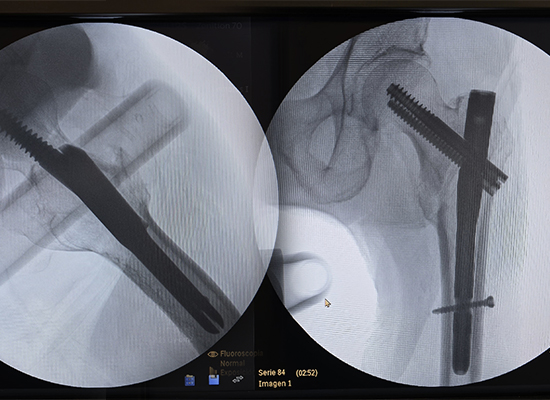

Radiographie postopératoire montrant la fixation par clou intramédullaire Intertan d'une fracture intertrochantérienne gauche, Pérou

Au cours de l'opération, le Dr Rivera a noté que le clou intramédullaire Intertan CZMEDITECH offrait une stabilité biomécanique supérieure et une implantation en douceur.

Après fixation, le patient a commencé une mobilisation assistée précoce. La douleur a été significativement soulagée, l'alignement des membres a été rétabli et les radiographies de suivi ont confirmé un positionnement stable de l'implant avec des signes de guérison progressive de la fracture.

Après réduction fermée et fixation par clou intramédullaire Intertan, le patient a obtenu une fixation stable de la fracture et une récupération fonctionnelle précoce. La douleur a été significativement soulagée, l’alignement des membres a été rétabli et l’imagerie de suivi a confirmé la bonne position de l’implant et la guérison progressive de la fracture.